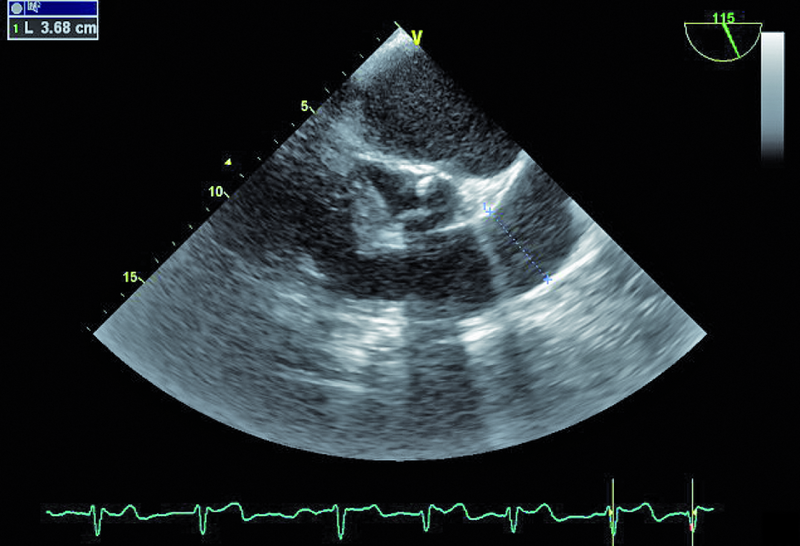

Mężczyzna, lat 79. Jakie patologie można rozpoznać na rycinach?

4. Rozległe zwapnienia płatków i pierścienia zastawki mitralnej (ryc. 4).

5. Przerost mięśnia lewej komory (ryc. 4, 5).

6. Skrzeplina w uszku lewego przedsionka (ryc. 5).